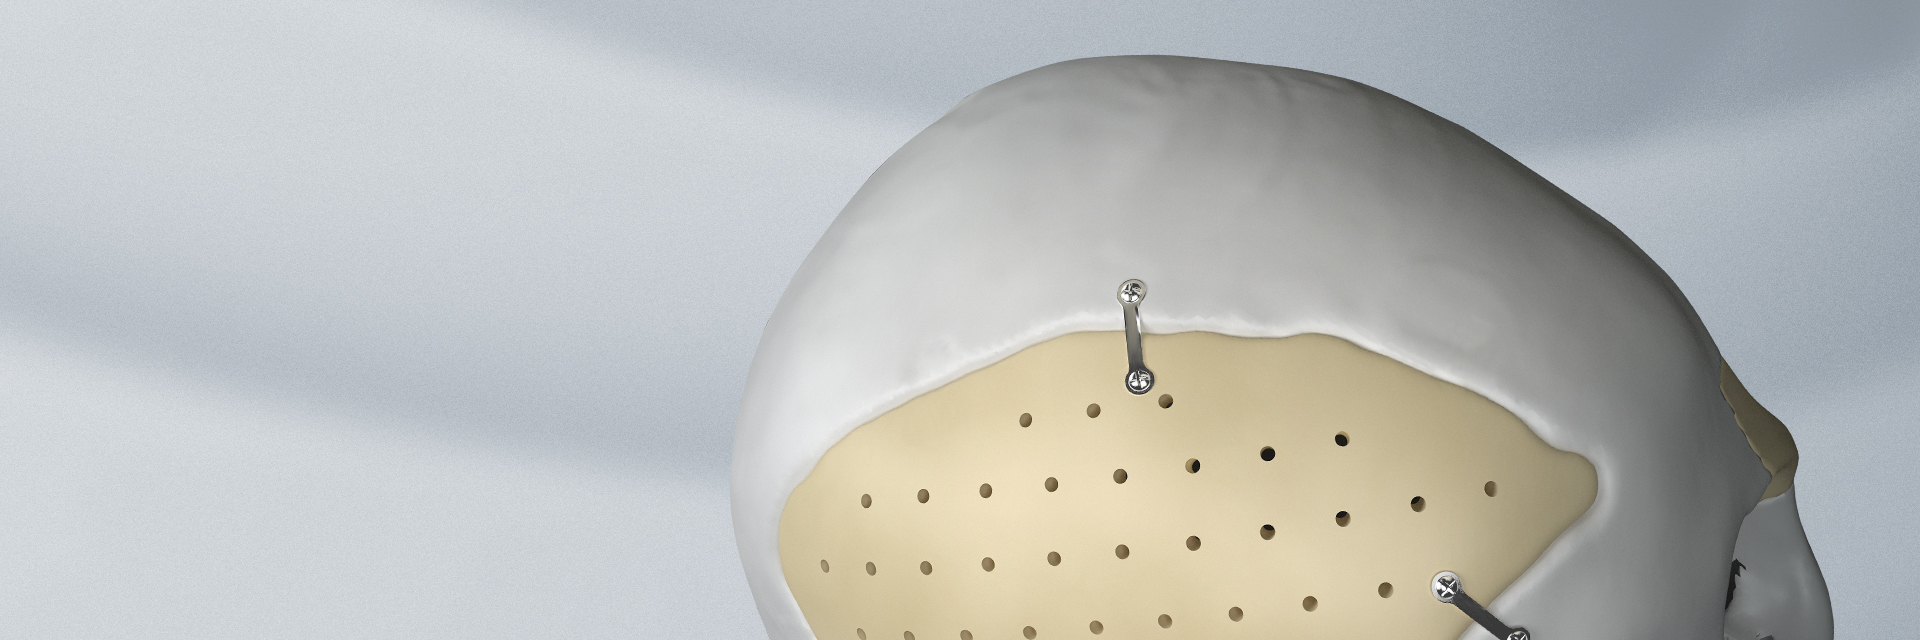

顱頜面內(nèi)固定鈦板 顱頜面內(nèi)固定鈦釘

顱頜面內(nèi)固定鈦板適用范圍

顱頜面內(nèi)固定鈦釘適用范圍